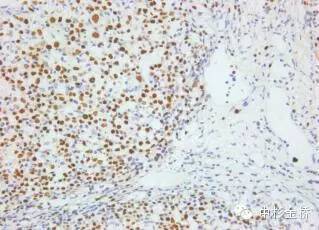

圖為EBER原位雜交染色DBA顯色,蘇木素復(fù)染

EBER是EB病毒編碼的小RNA,在EB病毒感染的細(xì)胞核中高拷貝存在。根據(jù)EBER的序列設(shè)計(jì)的EBER RNA探針,可以用于石蠟切片,具有較高的特異性和靈敏度,該試劑盒廣泛應(yīng)用于美國(guó)、歐盟等各國(guó)。

- DAB顯色,永久保存